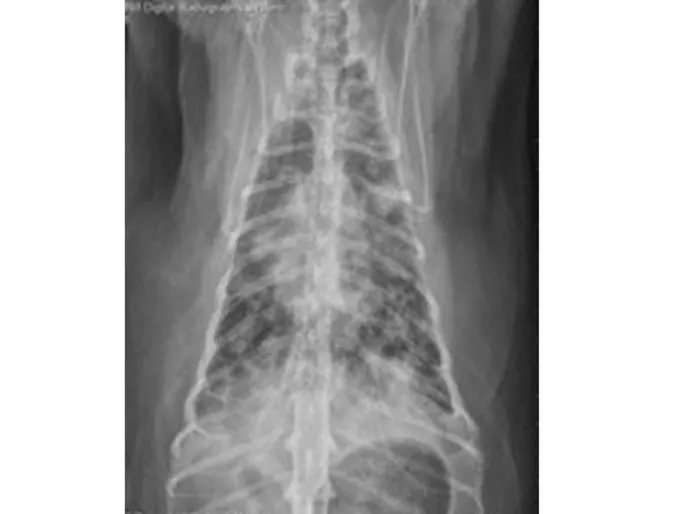

If the veterinary team is suspicious that a patient is bleeding, they will likely want to perform tests to further determine the underlying cause. Initial diagnostics performed may include electrocardiogram (ECG), blood pressure measurement, blood work, and imaging tests. Findings are often variable depending on the degree of bleeding. Generally, though, these tests will confirm the presence of anemia (low red blood cell concentration) due to blood loss, and imaging studies (x-rays and/or ultrasound) will confirm the presence of fluid in the abdomen. In some cases, an underlying reason for the fluid, such as a mass, may be visualized with abdominal ultrasound. A sample of the fluid may be obtained to confirm that the fluid is, in fact, blood. The veterinarian may take x-rays of the chest to check for any abnormalities, including signs of trauma if the animal is injured or evidence of tumor spread (metastasis) to the chest in non-traumatic cases (as an intraabdominal mass is the most common cause of bleeding in these cases). Finally, coagulation testing may be performed, if available, to rule-out a clotting disorder due to rodenticide (rat bait) ingestion or other diseases.